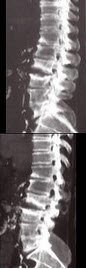

28、单项选择题

男,65岁,腰背部疼痛1月余,结合图像,最可能的诊断是()

A.脊椎结核

B.椎体压缩骨折

C.脊椎退行性变

D.脊椎转移瘤

E.L2~L3椎间盘炎